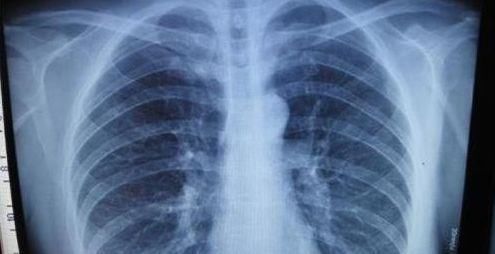

每日健康 【拍胸片能发现早期肺癌吗】每年的

拍胸片为何不能发现早期肺癌|肺癌| 发现_凤凰

早期肺癌筛查:胸片及痰液细胞检查均不可靠_早